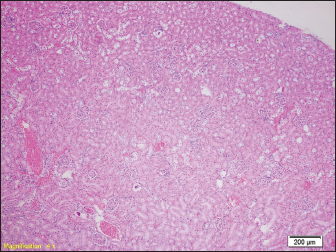

In the liver samples of all groups of rats, relatively uniform changes are observed, which in each sample include a certain degree of congestion, with overcrowding of the centrolobular veins, but also the veins of the portal spaces, as well as the dilation of the sinusoids filled with erythrocytes, while the hepatocytes in places show signs of fluffy degeneration (Figs. 5 and 6.)

Fig. 5. Blood filling of hepatic sinusoids and centrolobular vein (HE, ×100).

Fig. 6. Congested portal blood vessels as well as sinusoids, and hepatocytes with balloon appearance in places (HE, ×200).

However, studies have shown that there are statistical differences in the number of diatoms in false positive cases and actual drowning cases. Therefore, a comprehensive analysis of multiple organs, rather than just one organ, would be more useful for the diagnosis of drowning. Relatively uniform changes are observed in the liver samples of all groups of rats, which in each sample include a certain degree of congestion, with overcrowding of the centrolobular veins, but also the veins of the portal space, as well as dilation of sinusoids-filled with erythrocytes, while hepatocytes in places show signs of paper degeneration.